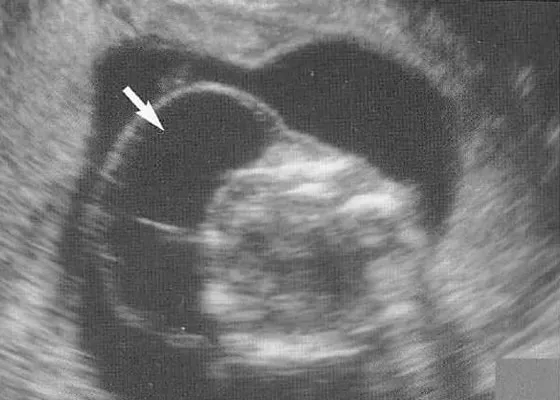

20代18トリソミー|健診で先生がNT肥厚と書いたのに説明してくれない

NIPTの後に赤ちゃんのNT肥厚(首の後ろのむくみ)が指摘